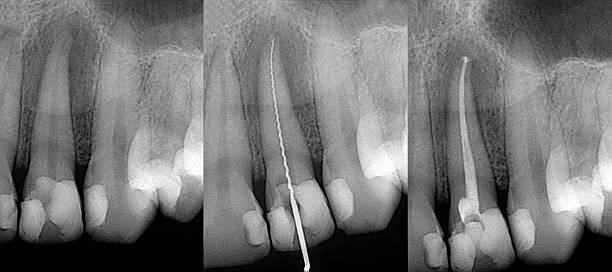

Root Canals Treatment Brampton

Root canal treatment Brampton

Root Canal Work, or Endodontic Dentistry, is conducted on the root and soft tissue beneath the tooth. Root Canal procedures may be needed even when the upper portion of the tooth appears normal and healthy, but disease, damage or infection is evident in soft tissue inside the root and around the root. As this area contains connective tissues, blood vessels and nerves, it’s necessary for the dentist to have undertaken additional specialist education in order to perform this work.

Root Canal treatment can require two visits to our clinic and uses local anesthetic to maintain the patient’s comfort throughout the procedure.